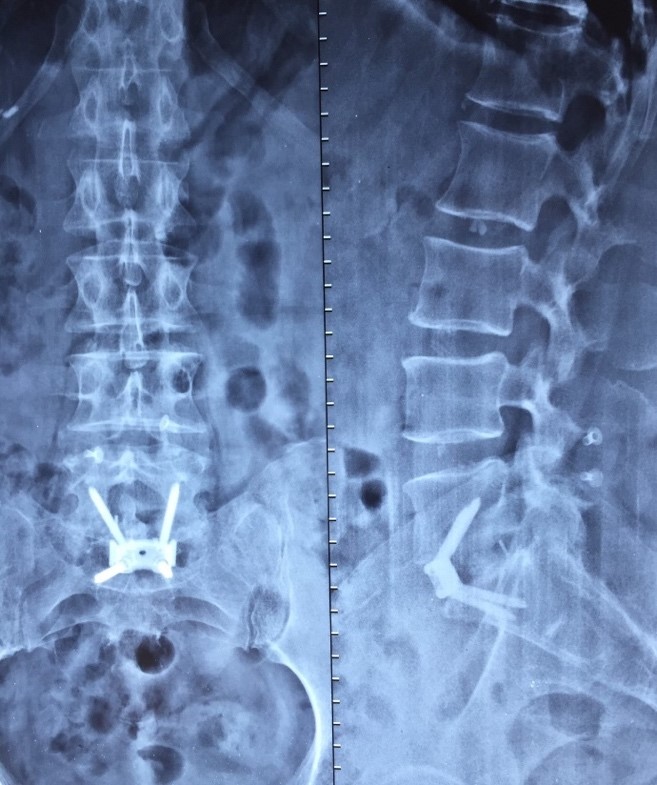

Radiografia da coluna lombar pós-operatória evidenciando o bom ganho de altura do espaço em L5S1.